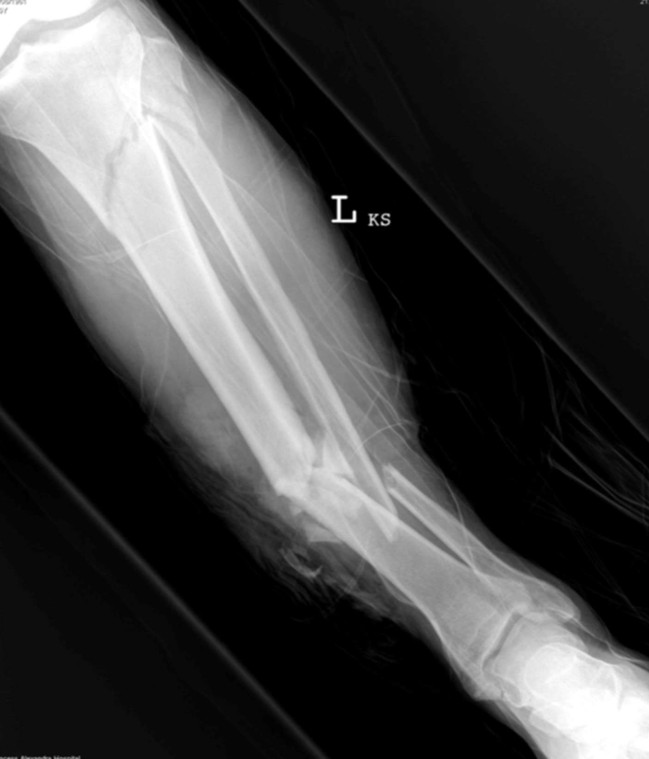

Rural open fracture

A 34-year-old man has been brought to your rural ED after falling out of a tractor on his farm. He …